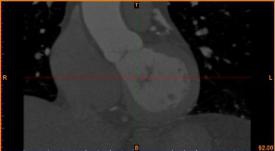

病例描述:

病人患冠心病,堵塞處較多,決定采用搭橋治療。

首先通過病人的心臟冠脈造影CT數據,獲取病人的心臟冠脈三維模型。

病人的冠脈造影CT數據                                              提取出的冠脈三維數據